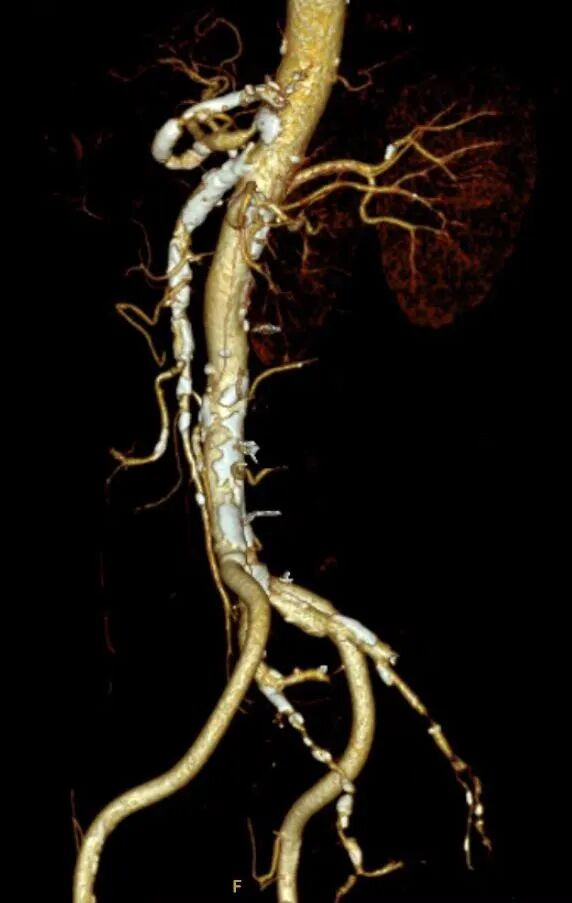

腹主动脉CTA:腹主动脉管壁见多发钙化、部分钙化斑块,管腔轻度狭窄。双肾动脉起始处见钙化斑块,管腔轻度狭窄,以远管腔显影可;腹腔干起始部可见部分钙化斑块,管腔狭窄程度约70%。脾动脉管壁见弥漫钙化斑块,管腔中-重度狭窄。肠系膜上动脉起始部见高密度支架,支架形态欠佳,局部腔内见多发钙化,管腔狭窄程度约70%。肠系膜下动脉见部分钙化斑块,管腔中度狭窄。

CTA重建